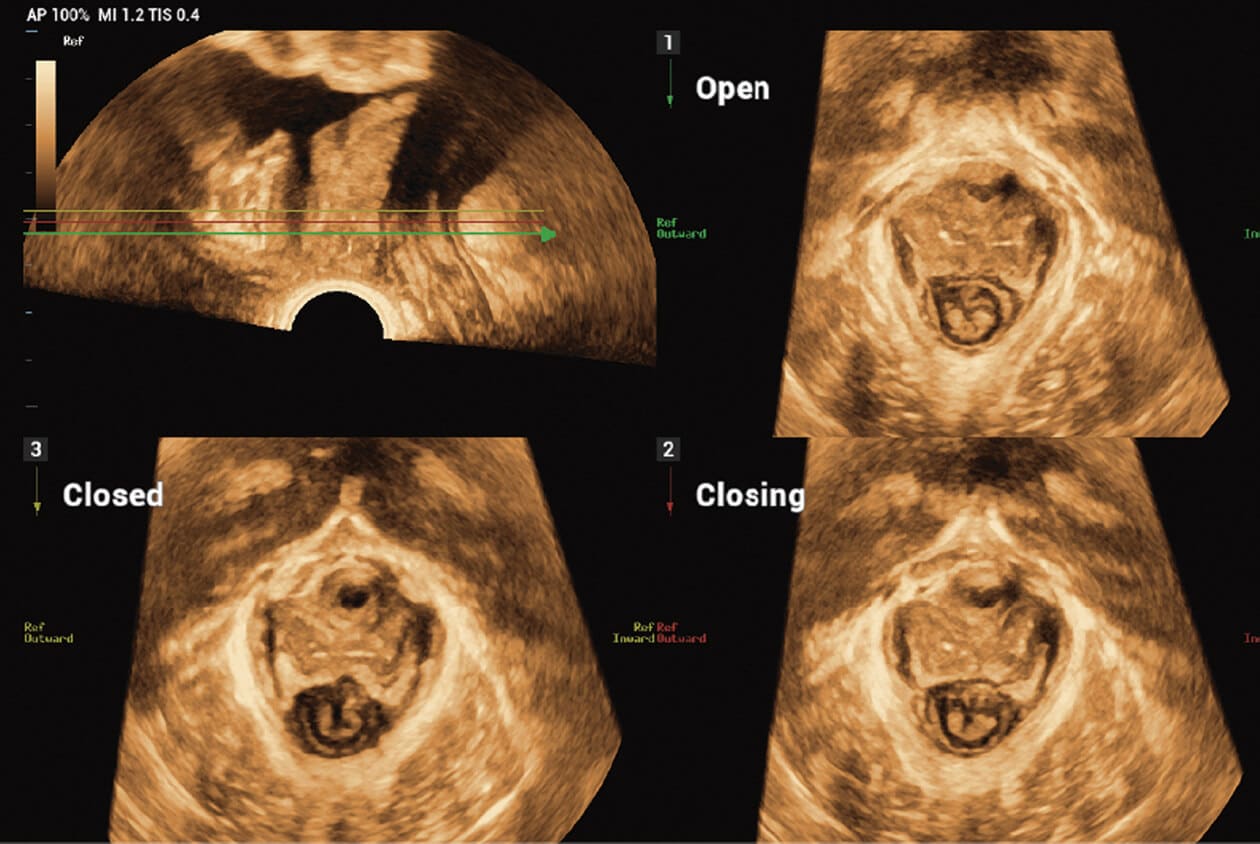

Powered by Mindray’s revolutionary ZONE Sonography (R) Technology+, the Imagyn I9 System boasts advanced ultrasound capabilities and leverages AI-inechanged technologies. The Imagyn I9 starts the process using auto clinical scenario identification, and uses automation at every point, from imaging optimization to planes scenario identification, and uses automation at every point, from imaging optimization to planes acquisition, quantification, and creating an automated workflow. The Imagyn I9 System provides a full-stack smart solution for efficient women’s health, covering wide-ranging applications from pre-pregnancy to obstetric to post-partum.